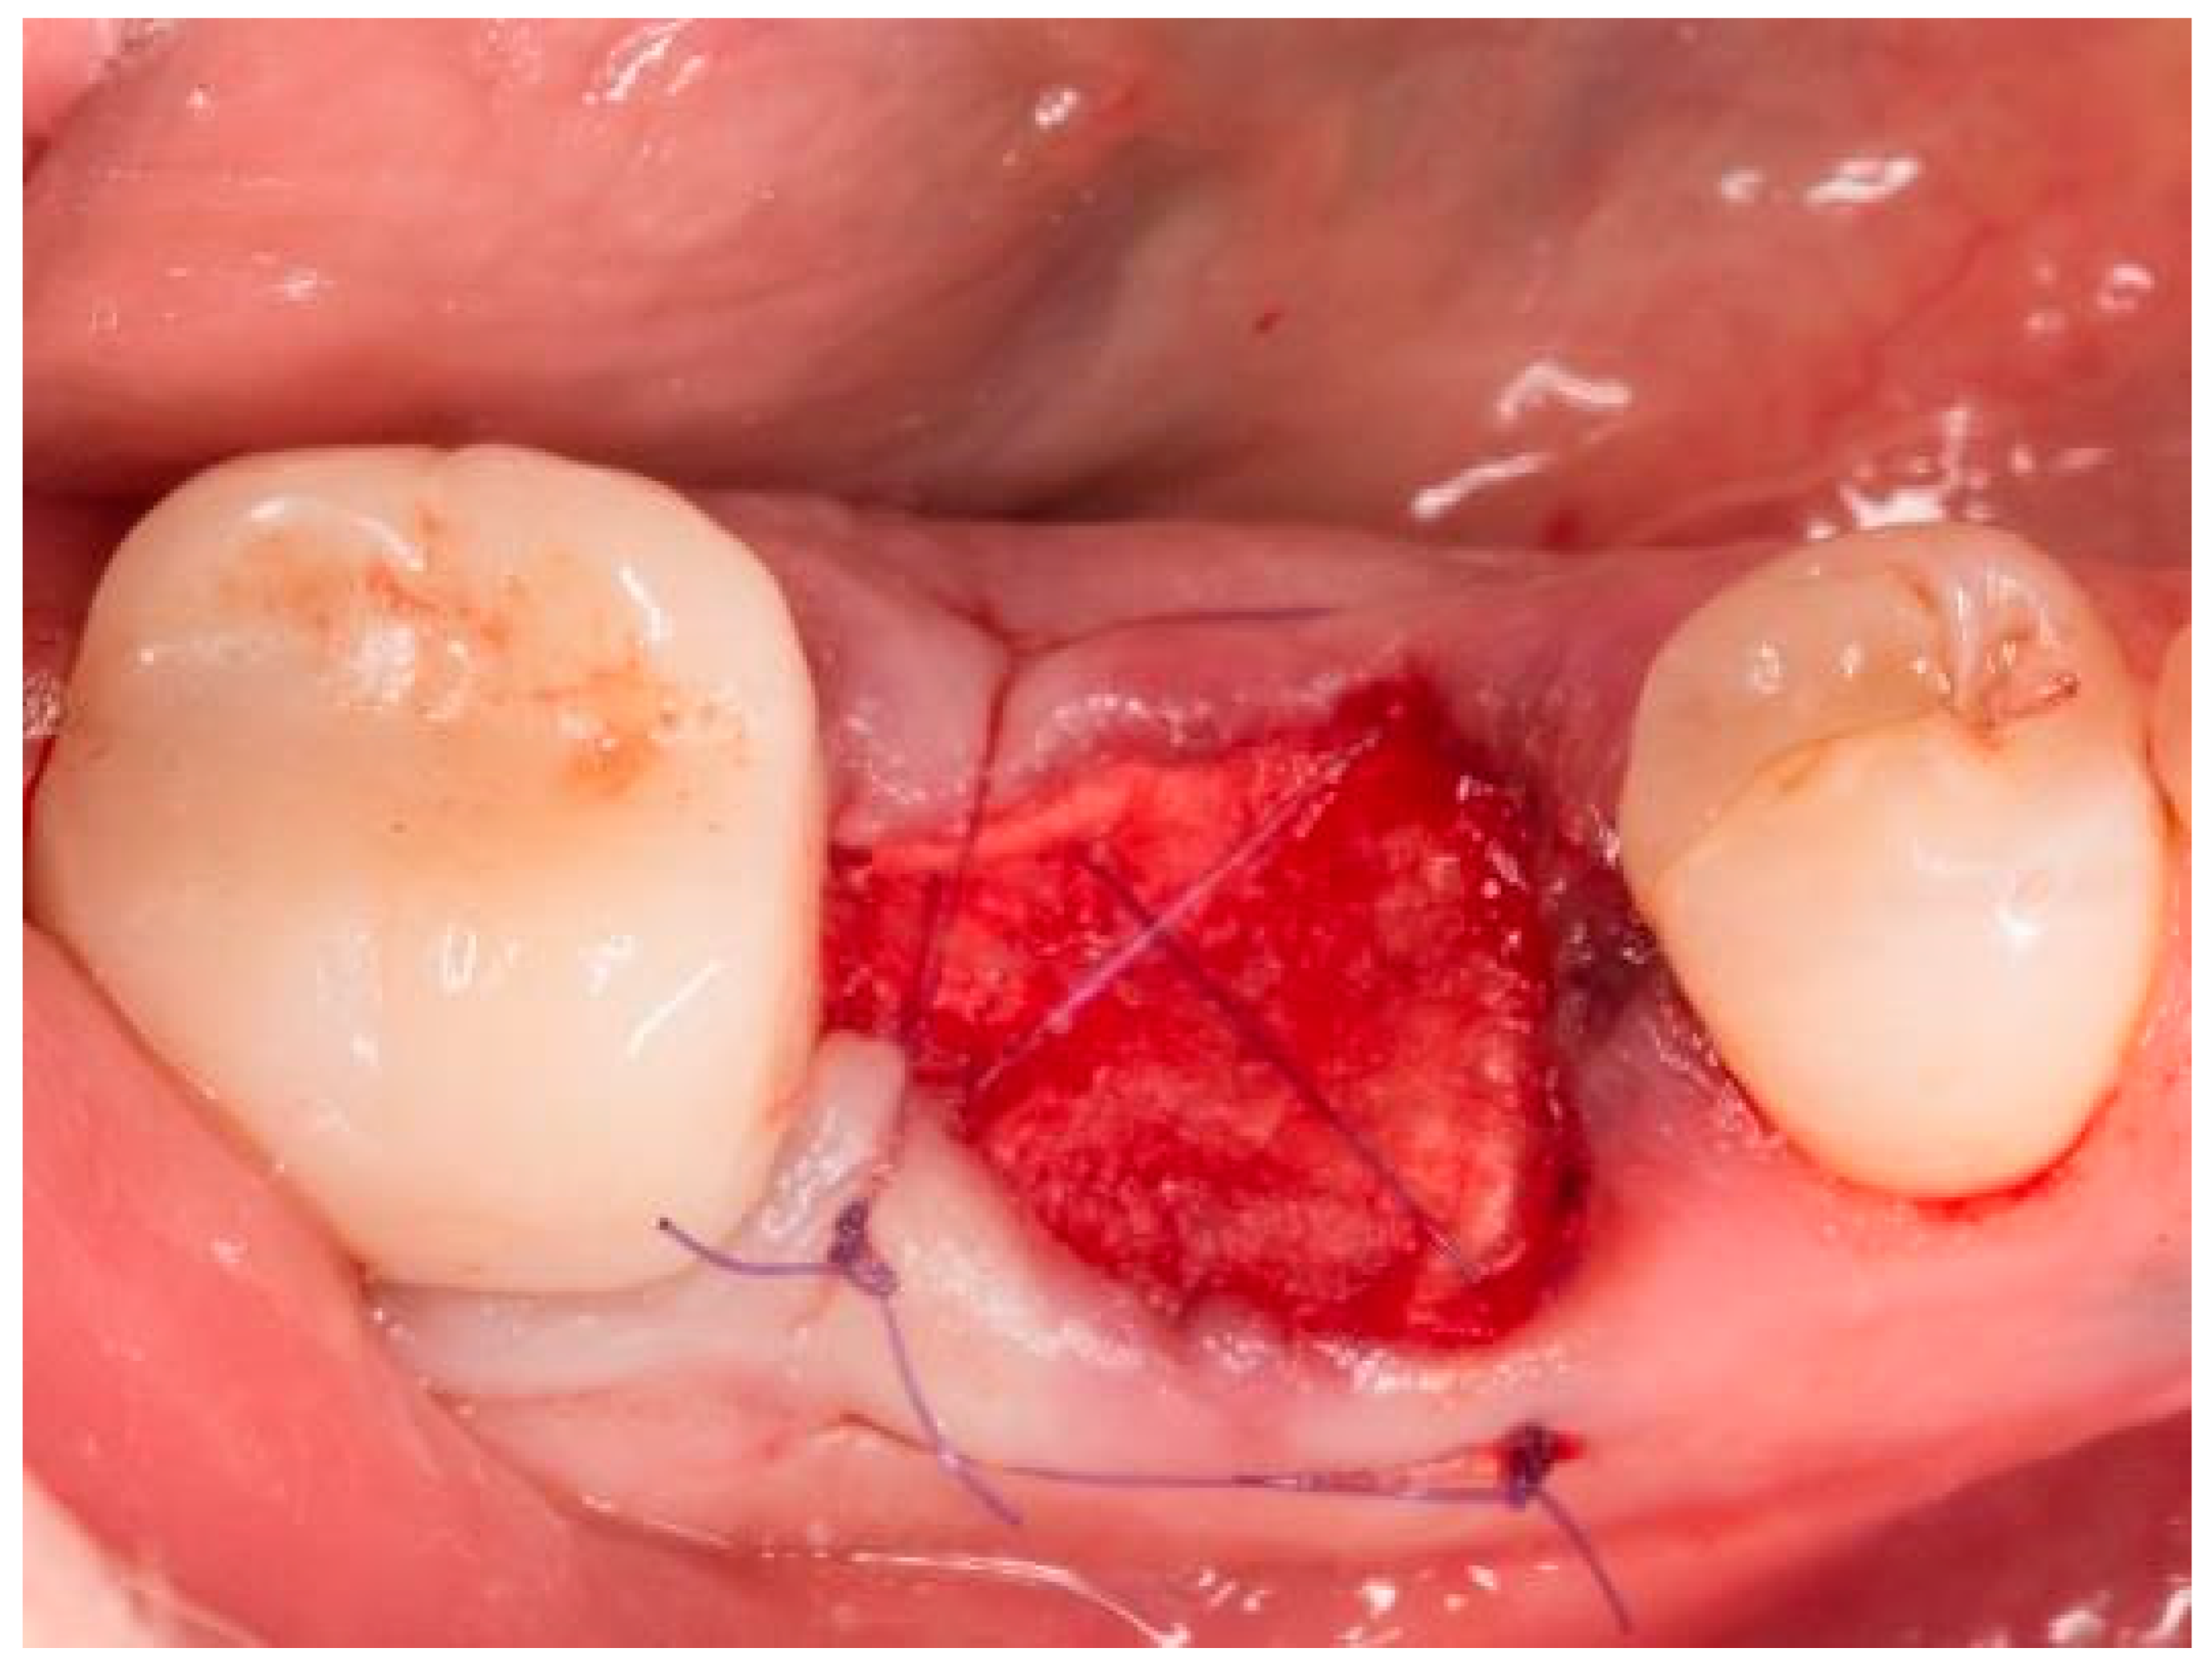

Figure 4.

Socket of tooth 46 after suturing.